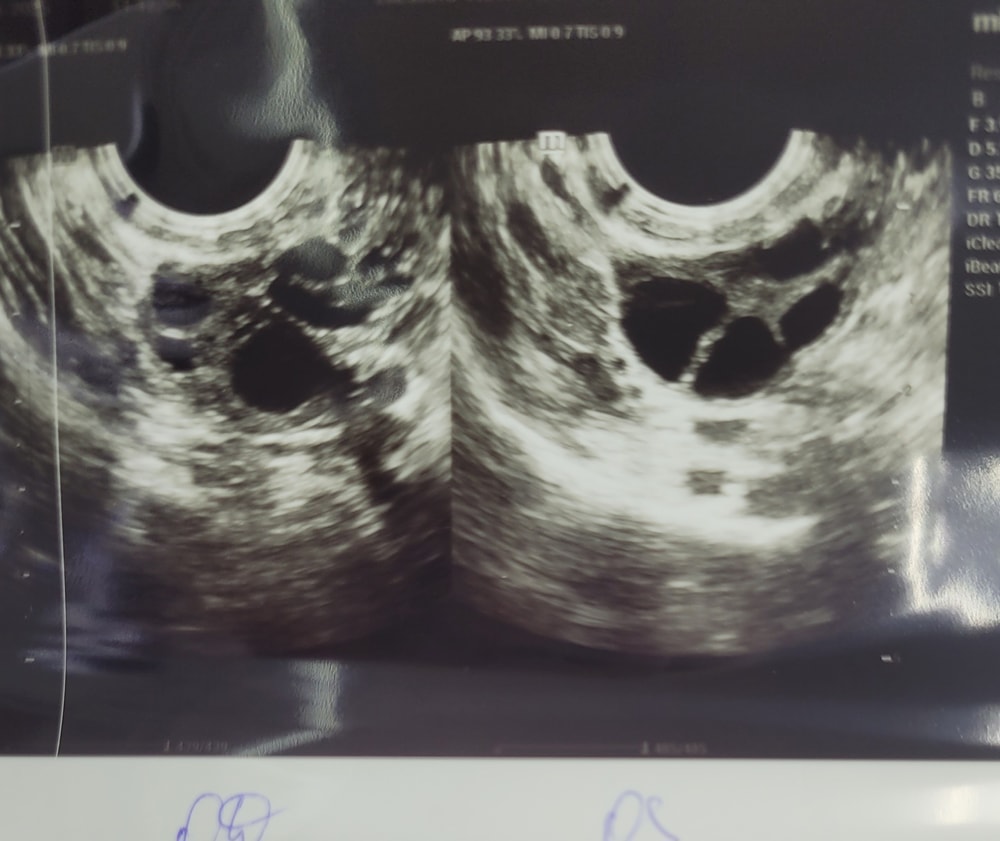

Девочки здравствуйте, подскажите пожалуйста, может было у кого похожее: стимуляция лорета с 4-9 дц, прогинова с 10 дц, сегодня по узи12 дц, эндометрий 10 мм, нашли двухкамерную кисту(((( и никакой овуляции...на 4 дц перед стимуляцией доминантный фолликул был в левом яичнике 11 мм, могло ли созреть рядом два фолликула? просто если посмотреть по снимкам узи на 4 дц и 12дц, как раз похоже, что выросли два фоликула и между ними тонкая полоска...или я просто себя успокаиваю(((((УЗИ на одном и том же аппарате